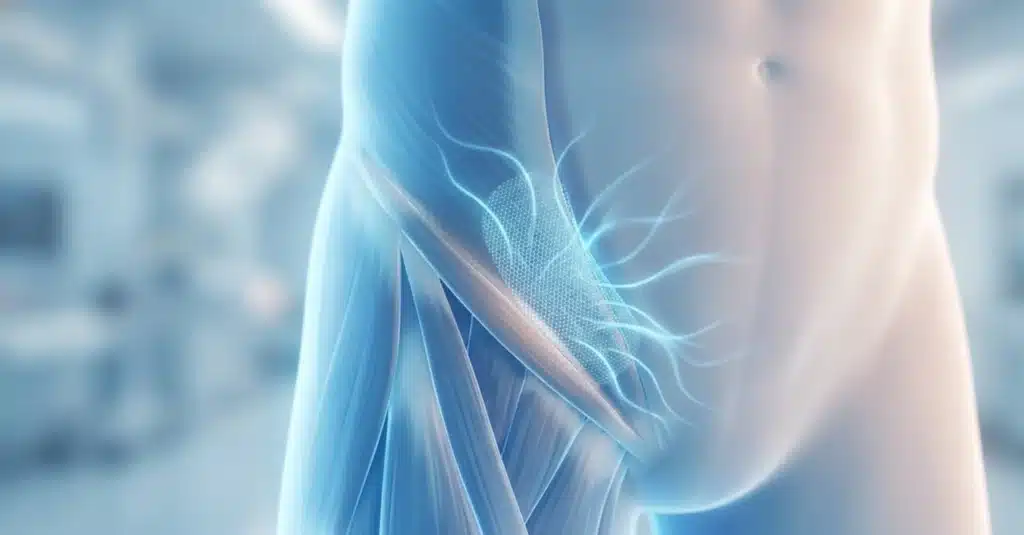

Es una de las preocupaciones más comunes que experimentan los pacientes meses o incluso años después de haberse sometido a una intervención: siento la malla. En la consulta en Costa Rica, recibo con frecuencia a personas que se alarman al notar un pinchazo sutil, una sensación de entumecimiento o la percepción de un “cuerpo extraño” […]